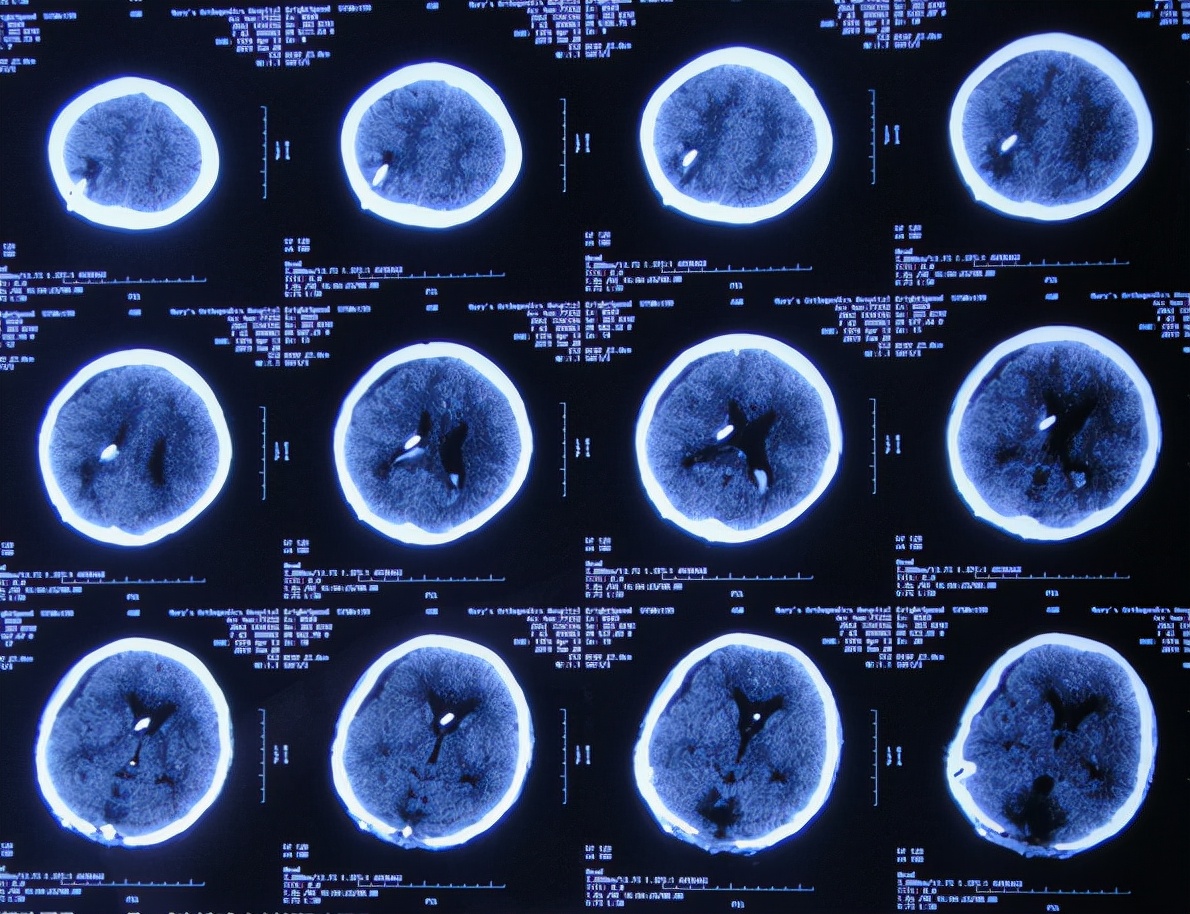

入院治疗3天即2019年6月24日,进行了脑室腹壁外引流术,术后当天查头颅CT示脑室引流状态( 图-18 )。

图-18: 2019年6月24日头颅CT

入院治疗6天即2019年6月27日,查头颅CT示脑室缩小( 图-19 ),但有少量出血,当天给予脑室引流管调整术。

图-19: 2019年6月27日头颅CT

术后次日复查头颅CT示引流管位置良好( 图-20 )。

图-20: 2019年6月28日头颅CT

入院治疗10天即2019年7月1日,复查头颅CT示脑室缩小、出血基本消失( 图-21 )。

图-21: 2019年7月1日头颅CT